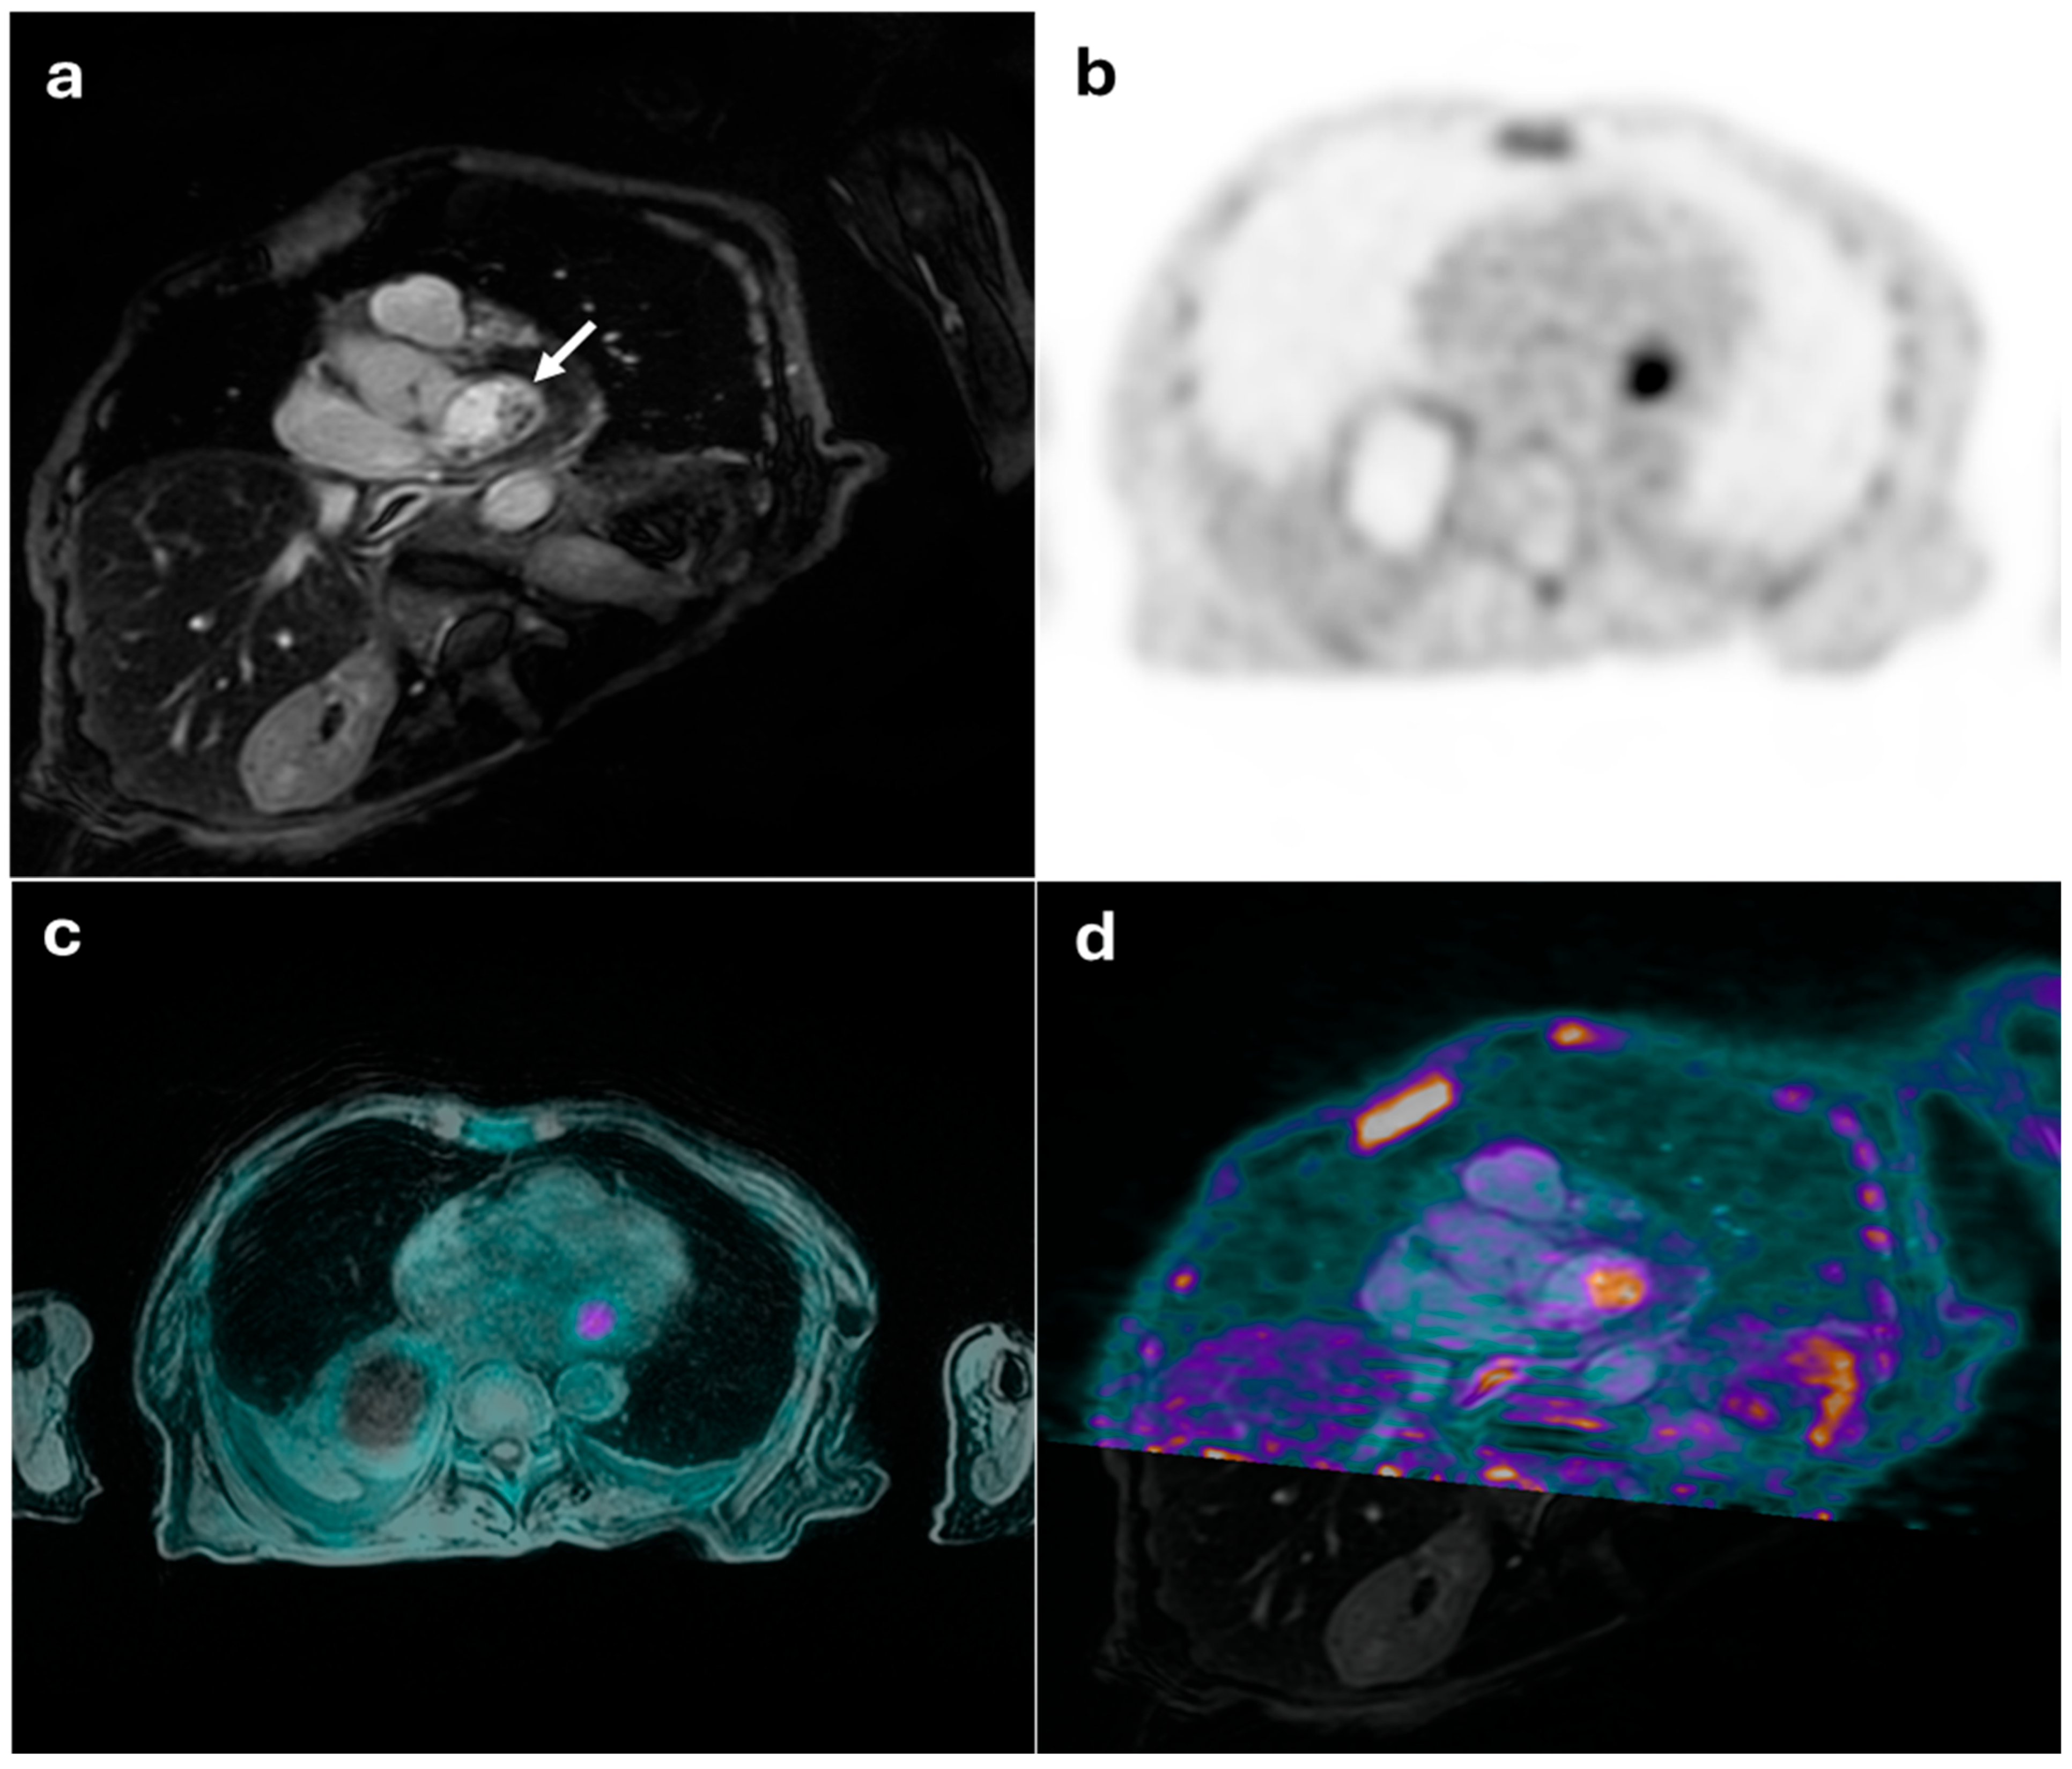

Figure 1.

45-year-old female with suspected mitral valve endocarditis. (a) shows a cardiac MRI image revealing a mobile pseudonodular lesion on the posterolateral leaflet of the mitral valve, exhibiting late gadolinium enhancement (white arrow), which was inconclusive for the presence of inflammatory vegetation. (b) displays an FDG-PET image with pathological radiotracer uptake (SUVmax: 6.5). The integrated PET/MRI findings were diagnostic of mitral valve endocarditis (c,d).